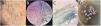

En todos los pacientes de la serie se obtuvieron imágenes tricoscópicas (fig. 1A) y de los exámenes directos con KOH y cultivos micológicos (figs. 1B-D). Las manifestaciones clínicas observadas incluían lesiones eritematodescamativas en regiones occipital y/o temporales clínicamente muy similares a la psoriasis o a la dermatitis seborreica, motivo por el que previamente habían sido en ocasiones tratadas con corticoides tópicos con empeoramiento de las lesiones (fig. 2A, y ver también uno de los casos más llamativos de la serie incluido en el panel B de la figura 2 de la referencia6). Las TC connubiales de pacientes infectados en peluquerías también fueron frecuentes. Con menor frecuencia, se apreciaron pacientes con TC de puntos negros (fig. 2B) y TC inflamatorias (fig. 2C). No fue extraño encontrar que muchos de estos pacientes (especialmente aquellos con formas de TC de puntos negros) eran portadores asintomáticos, siendo de gran ayuda para su detección la tricoscopia7. Igualmente, se detectaron casos aislados de pacientes simulando una alopecia areata y una costra láctea en la paciente más joven de la serie (fig. 2D), cuyo padre, con TC diagnosticada en la clínica y adquirida en peluquería, la había contagiado. Todos los casos (cuya presentación queda resumida en la figura 2E) fueron declarados en la Delegación Provincial de Salud de Málaga con objeto de localizar los centros donde se habían producido los contagios y frenarlos.